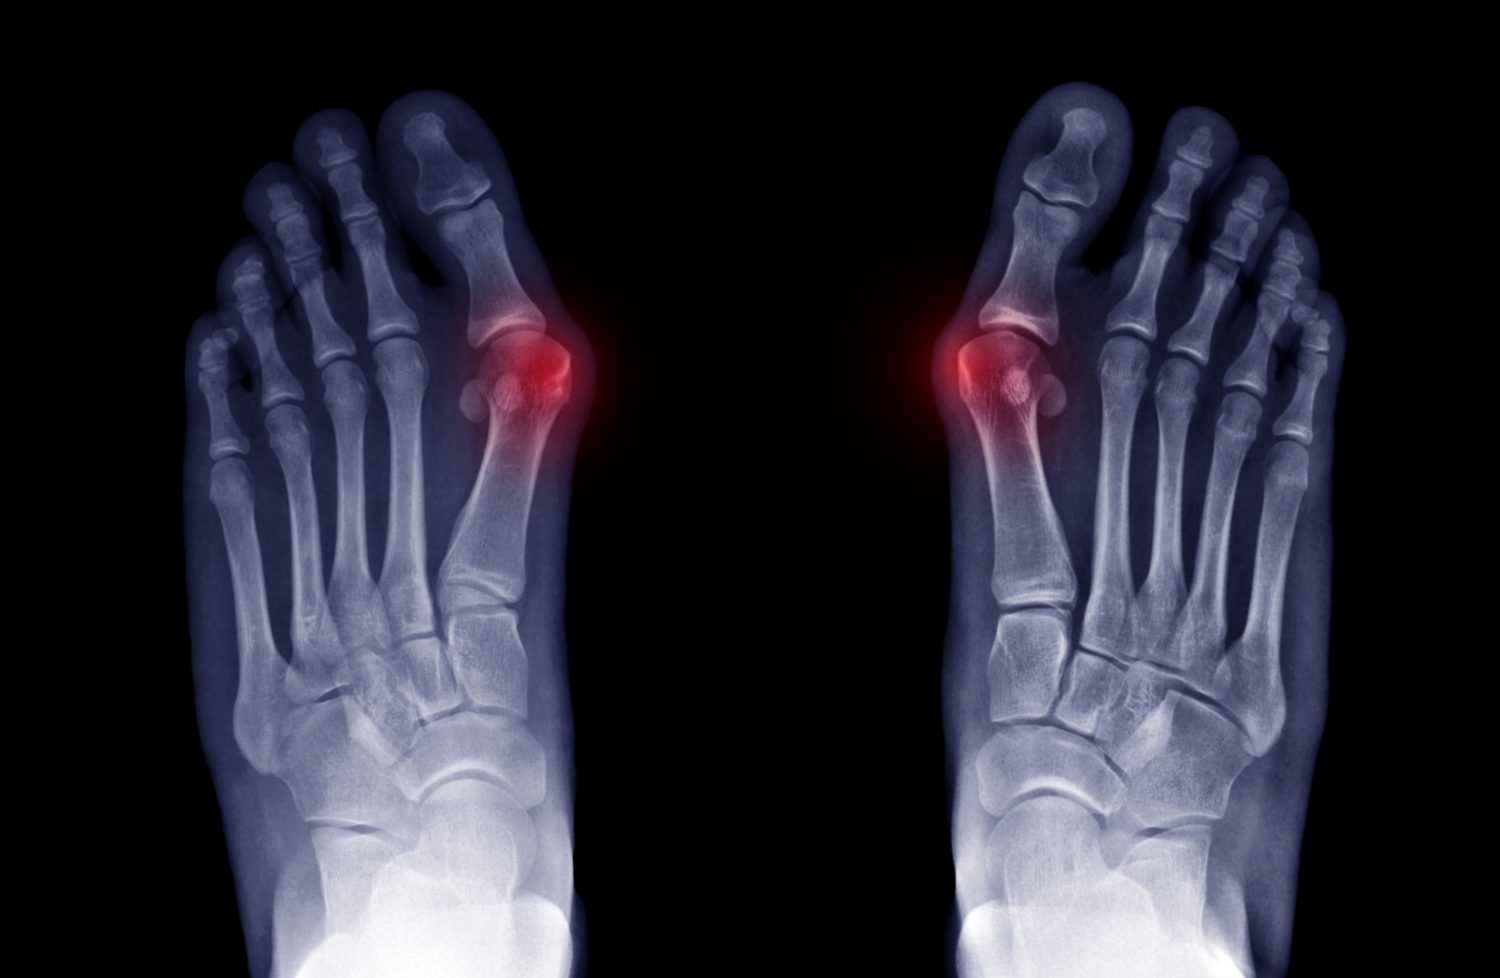

Vbočený palec se netýká pouze samotného palce, jak se může někdo mylně domnívat. Jedná se o komplexní postupující statickou deformitu přednoží, kdy dochází k vnitřní rotaci první nártní kůstky, jejímu odklonění směrem ven od ostatních kostí, proximální (blíže k tělu / blíže ke kotníku) článek palce se vybočí směrem dovnitř a celý prstec může i rotovat na vnější hranu.

V oblasti hlavičky prvního metatarzu (první nártní kost) se tvoří tzv. bunion, kostěná exostóza (výrůstek). V tomto místě probíhají také zánětlivé procesy, které bývají bolestivé, kůže u kloubu je zarudlá, často i teplá.

Zpravidla se zde objevují také artrotické změny a u některých případů i osteofyty (kostěné výrůstky přímo v kloubu). Oba tyto problémy do budoucna mohou způsobovat další komplikace, jako je hallux limitus či rigidus (omezená hybnost palce, úplná nehybnost palce).